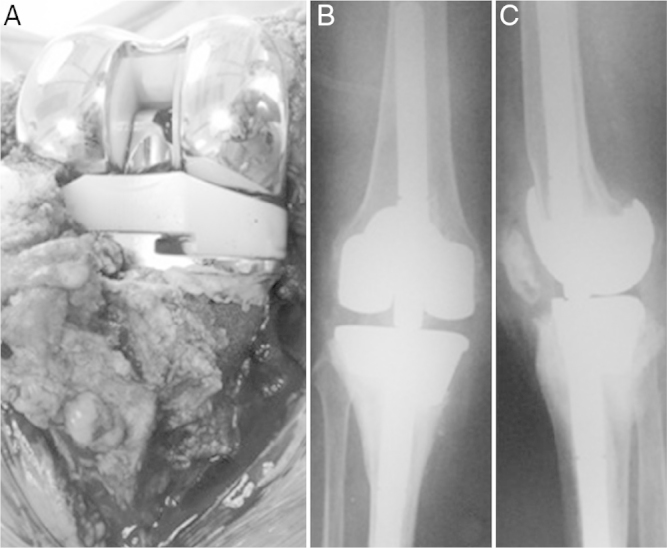

Areas between the external surface of the tantalum cone and the host bone were grafted using autologous bone coming from the cuts that had been made. The internal surface of the trabecular cones reconstituted the proximal metaphyseal region of the tibia or the distal region of the femur and acted as a surface for cementation of the definitive prosthetic components, using intramedullary nails (Fig. 2A–C).

Fig. 2.

Tantalum cone in proximal tibia with autologous graft on external surface (A), cementation in interior (B), with implantation of the tibial component (C).

Radiographic results

Comparison of the sequential radiographic examinations showed that there was a trabecular bone reaction at the interface between the host bone and the trabecular metal and absence of radiolucency lines between the cone and the host bone in these seven patients. These features constituted signs of osseointegration of the implant.

We did not observe any loss or migration of the trabecular metal cone or prosthetic components in any of the patients. No signs of osteolysis were observed in the cases evaluated. During the radiographic follow-up of our sample, we have so far not identified any radiolucency lines that would constitute loosening of the implants (Fig. 3).

Fig. 3.

Final implant with tantalum cone (A), postoperative X-rays (B and C).